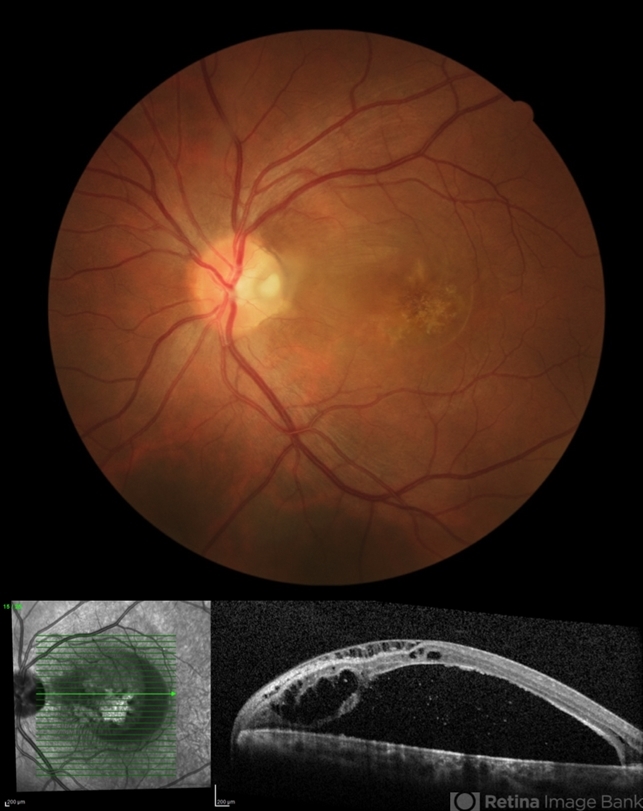

- optic pit, maculopathy

- Fundus photograph and spectral-domain OCT of an 43-year-old male with left eye optic pit maculopathy.